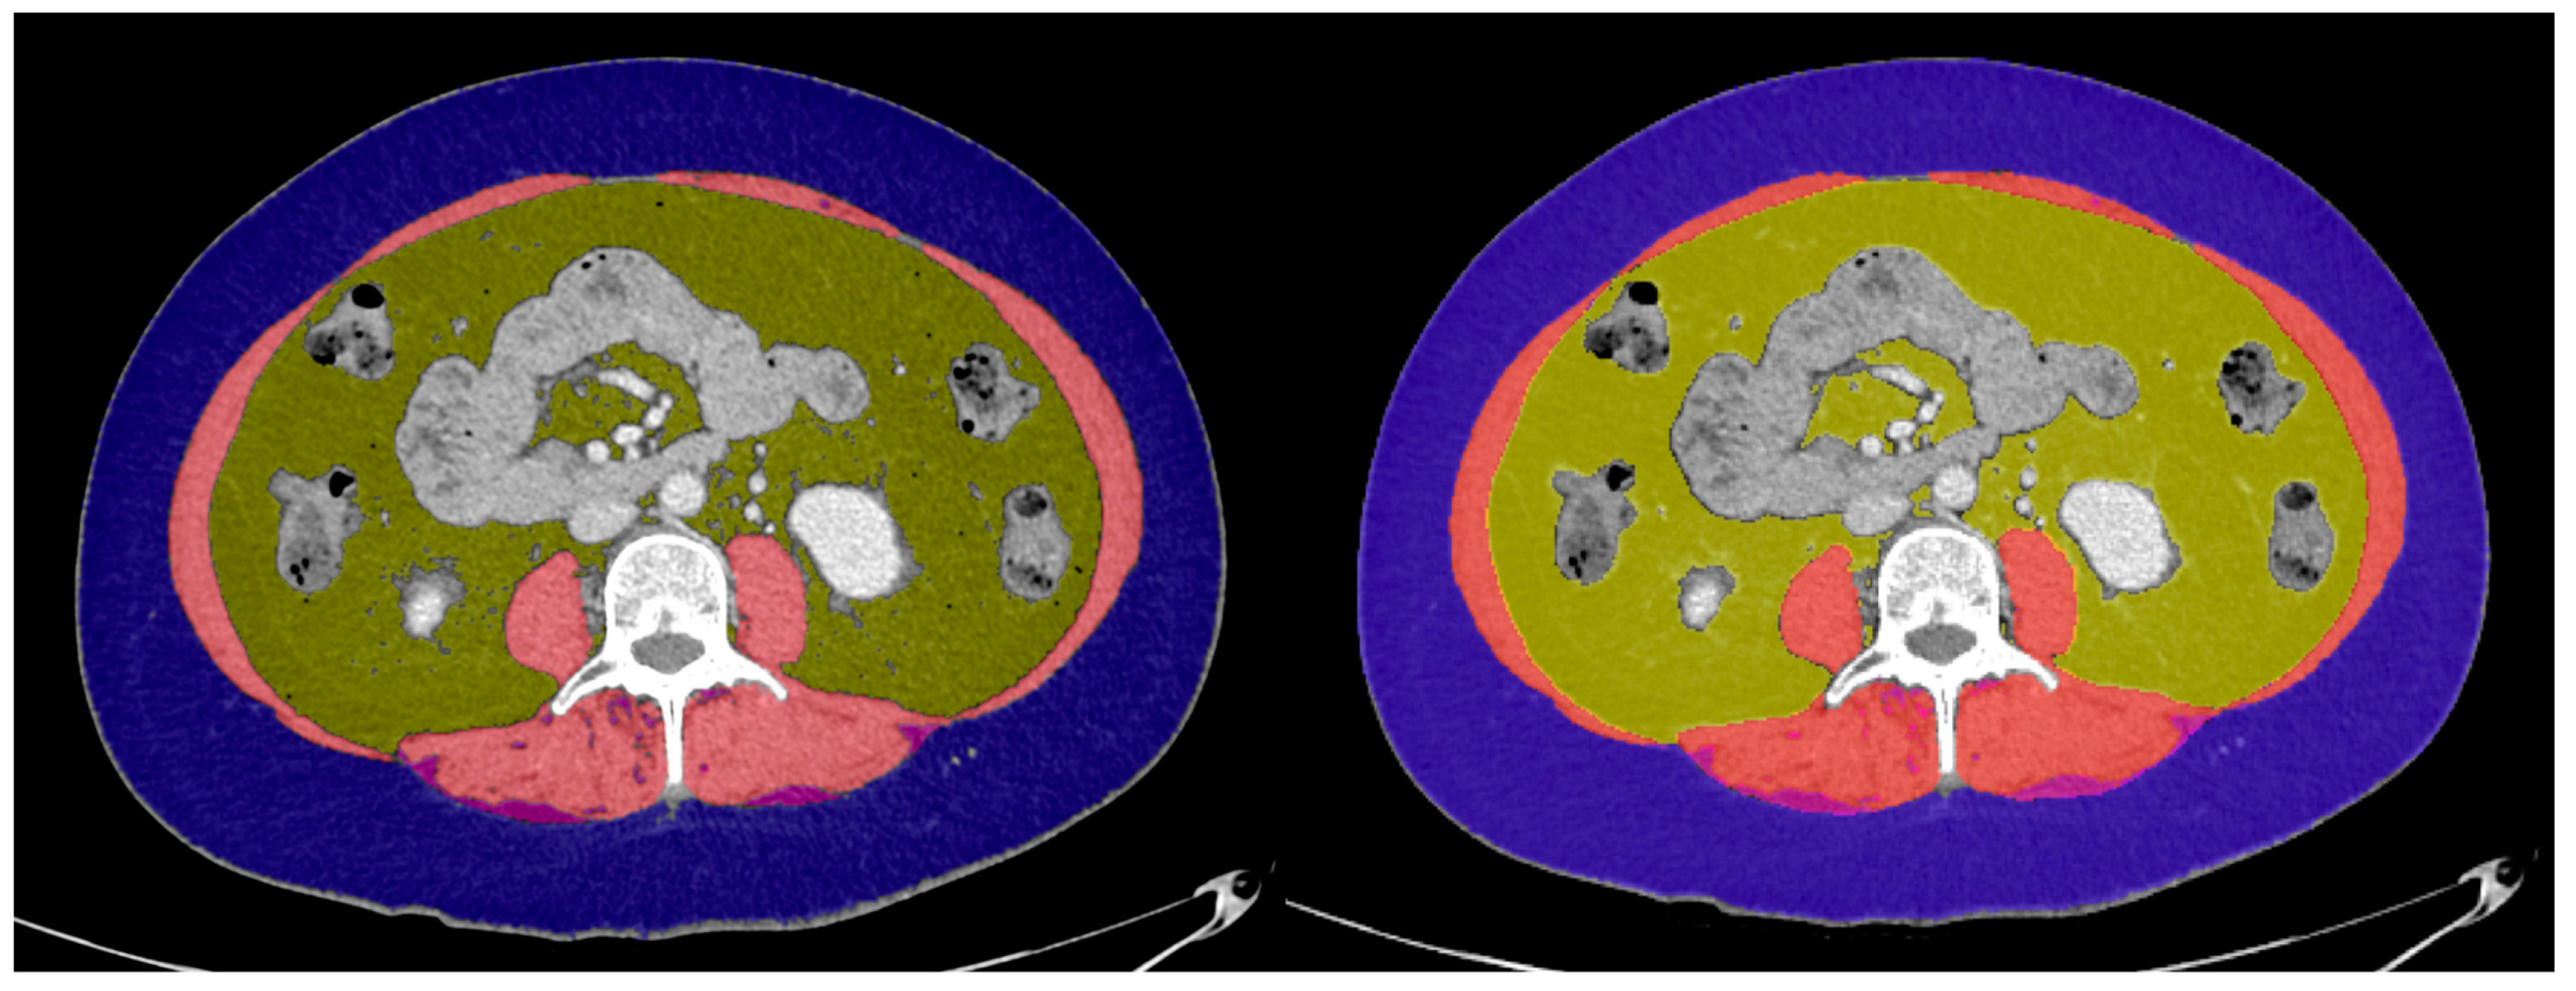

2.2.1. Image Analysis